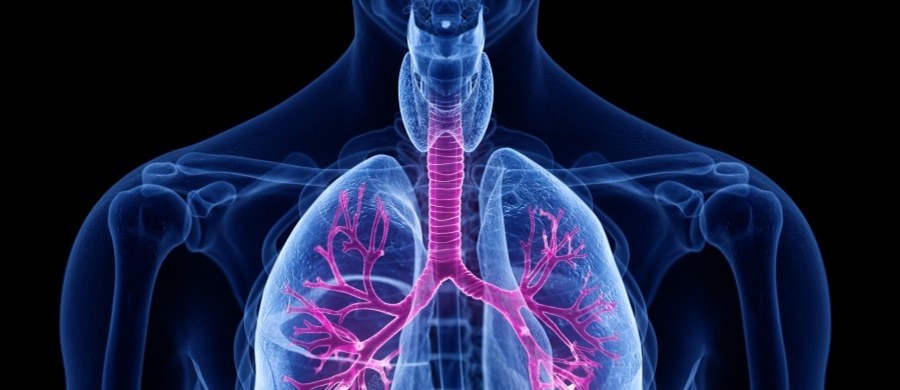

Układ oddechowy odpowiada za dostarczanie tlenu do organizmu i usuwanie dwutlenku węgla. Aby działał sprawnie, warto dbać o jakość powietrza – regularnie wietrzyć pomieszczenia, unikać dymu tytoniowego i […]